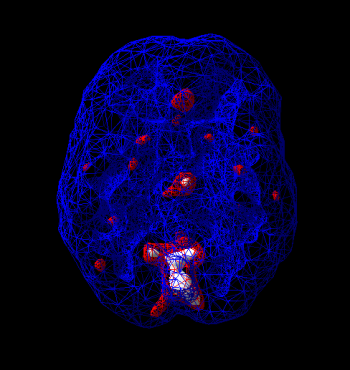

IV.4.6. SPECT – A szcintigráfiatomográfos alkalmazása

- IV.4. Nukleáris diagnosztika